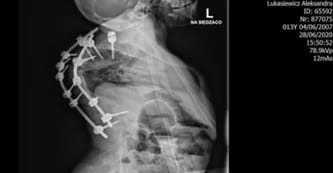

Mam głęboką kyfoskoliozę - skomplikowane skrzywienie kręgosłupa, wynoszące około 160 stopni - a do tego garb żebrowy... To hamuje rozwój mojej klatki piersiowej i sprawia, że narządy mają bardzo mało miejsca... Kręgosłup uciska je, przesuwa, co powoduje straszliwy ból... Najgorsze jest. to, że zmiażdżeniu ulegają płuca. Już teraz w nocy muszę oddychać przy pomocy respiratora, bo brakuje mi tlenu. Ucisk może w końcu sprawić, że któregoś dnia przestanę oddychać i po prostu się uduszę... Strasznie się tego boję! Mam dopiero 14 lat, chcę żyć!

Cała operacja będzie bardzo ryzykowna i skomplikowana. Najpierw zostanie usunięty obecny implant, który dwukrotnie już przebił mi się przez skórę i musiał zostać skrócony, przez co górny odcinek kręgosłupa nie jest już chroniony. Lekarze natną mój kręgosłup i usuną jeden krąg... Następnie zastosują specjalny wyciąg halo - do mojej głowy zostanie przykręcona obręcz, przy pomocy której będą podwieszane ciężary celem wydłużenia i rozprostowania kręgosłupa. Po kilku miesiącach przejdę jeszcze jedną operację polegającą na założeniu nowego implantu.